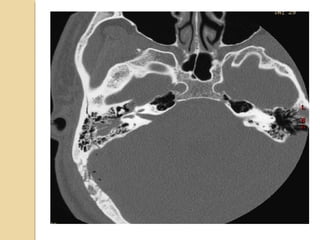

TEMPORAL BONE FRACTURESTEMPORALBONE FRACTURES Look for opacification of the mastoid Longitudinal: 70%, parallel to long axis of petrous bone, conductive hearing loss (from ossicular dislocation), facial nerve paralysis (20%) Transverse: 20%, sensorineural hearing loss, facial nerve paralysis (50%) Complex Complications: meningitis, abscess